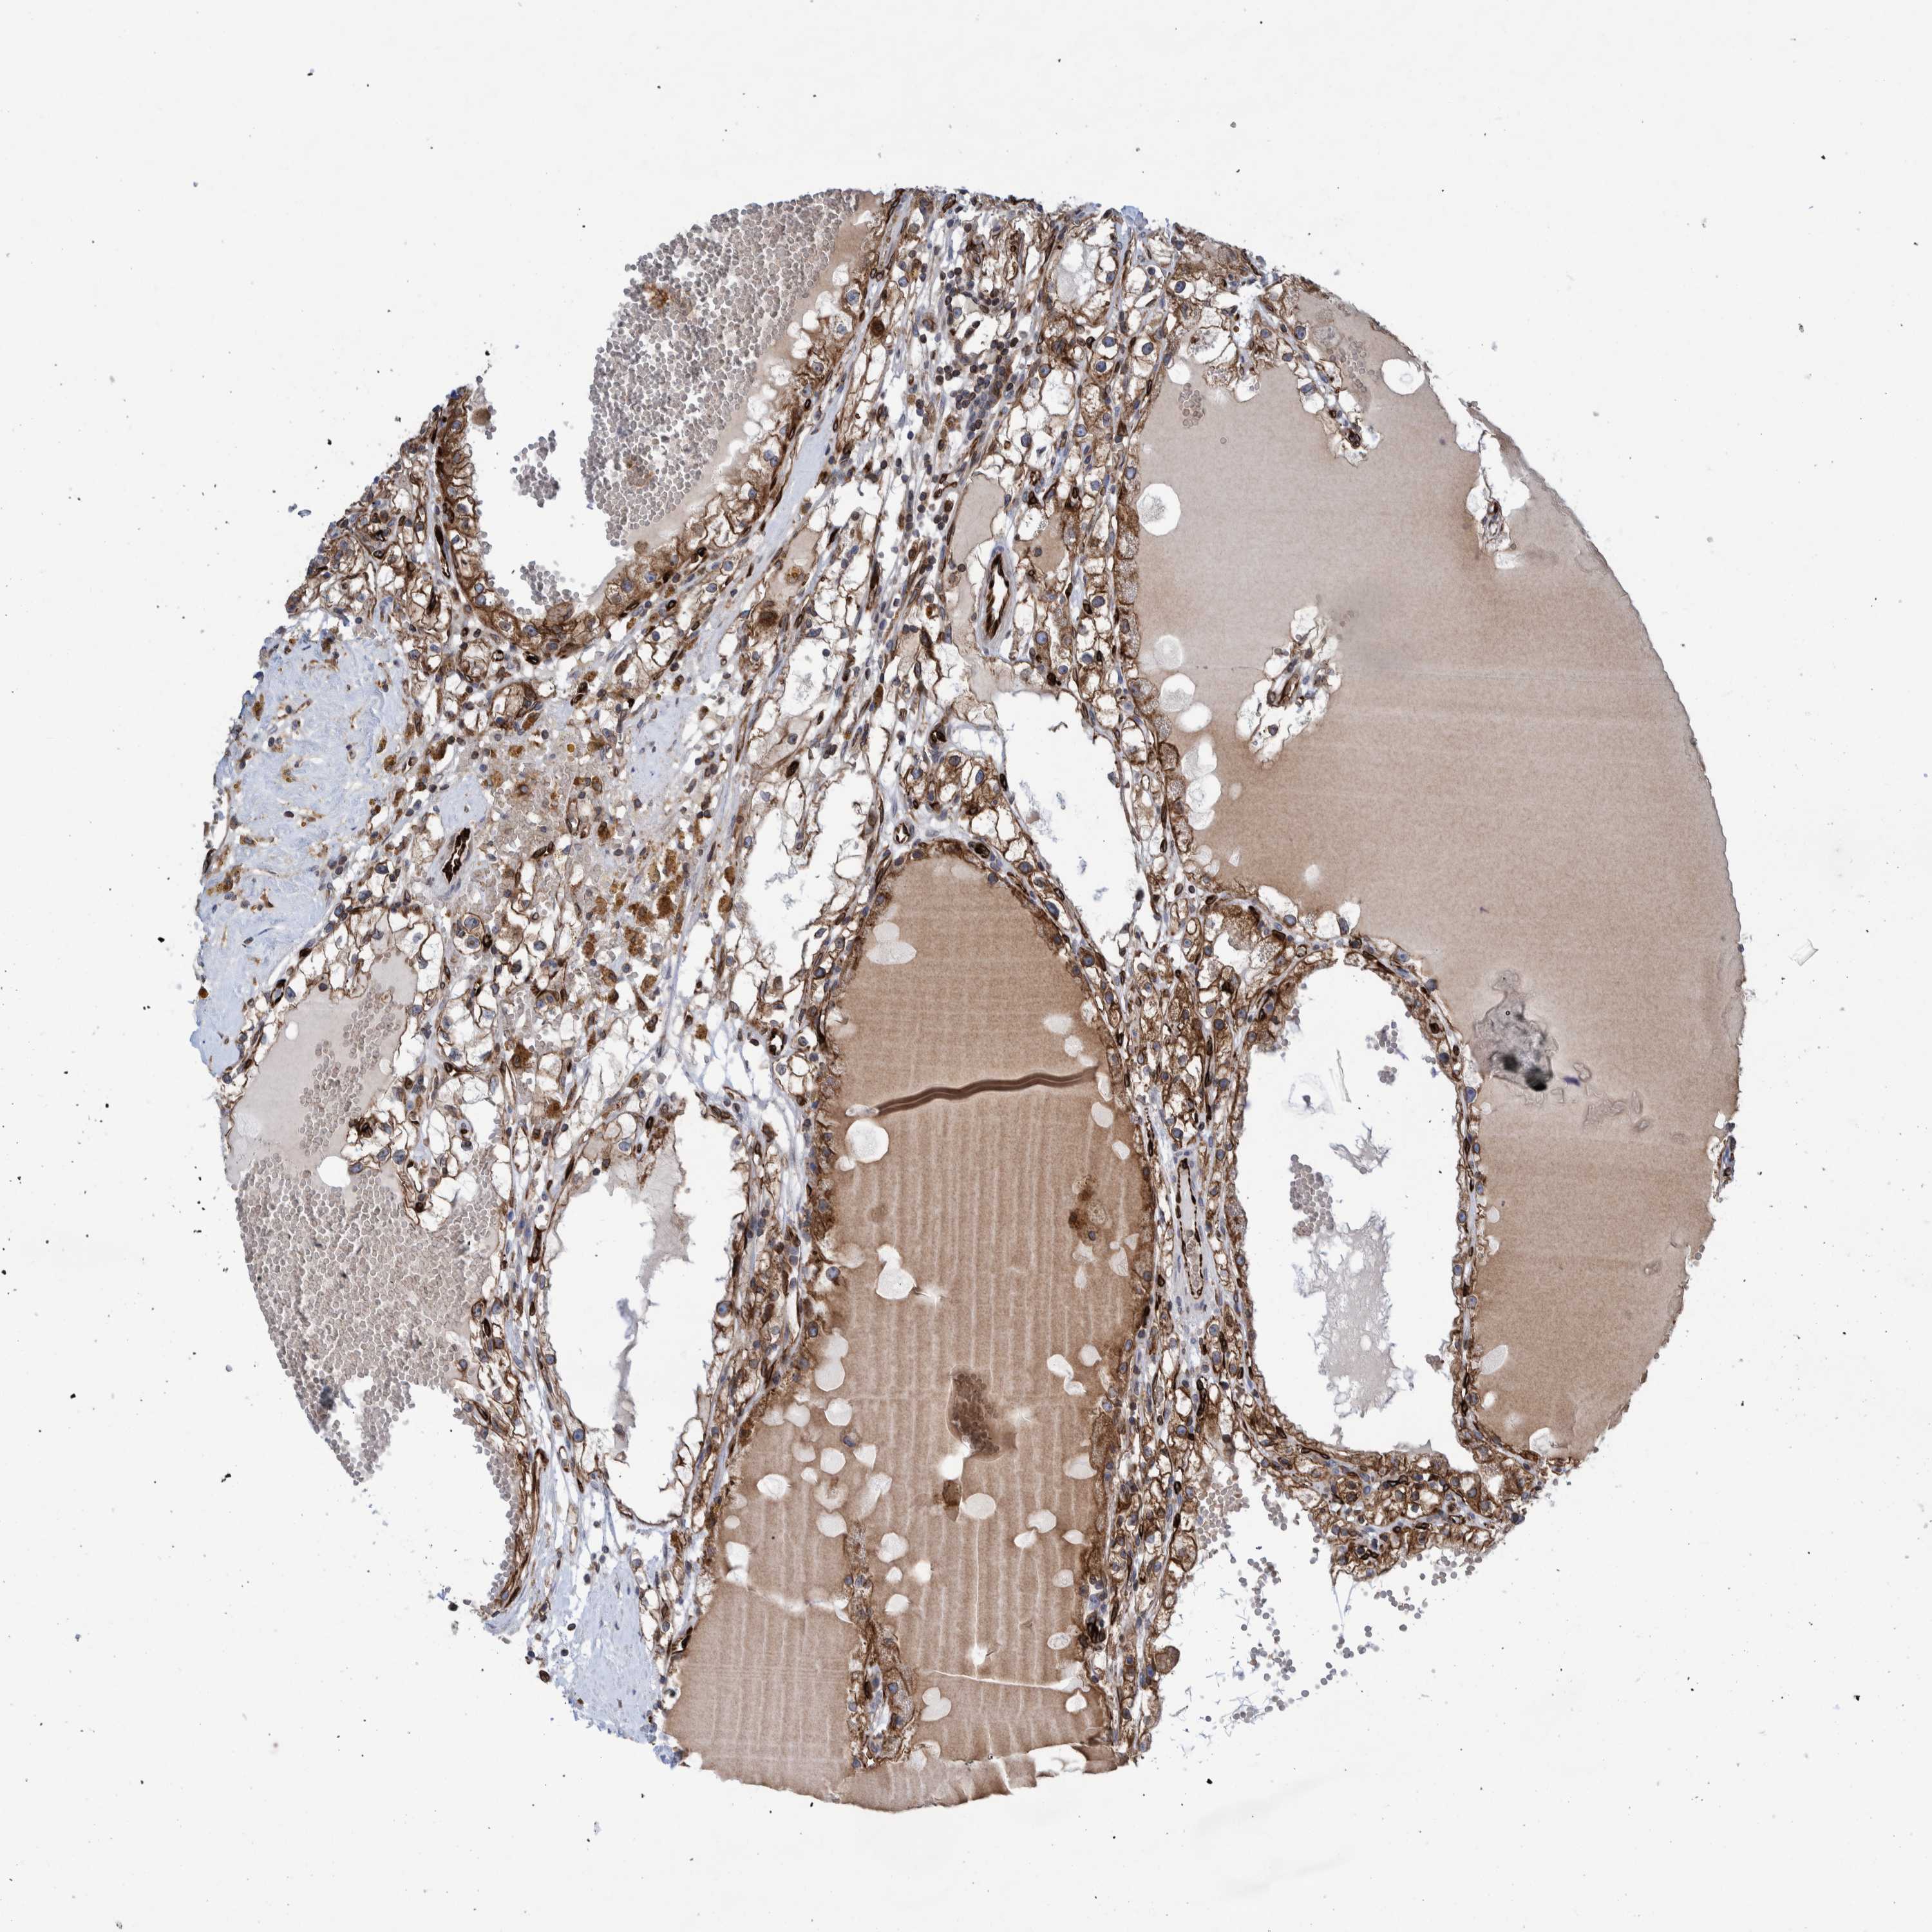

KIDNEY RENAL CLEAR CELL CARCINOMA (VALIDATION) - Interactive survival scatter ploti

The Survival Scatter plot shows the clinical status (i.e. dead or alive) for all individuals in the patient cohort, based on the same data that underlies the corresponding Kaplan-Meier plots. Patients that are alive at last time for follow-up are shown in blue and patients who have died during the study are shown in red.

The x-axis shows the expression levels (FPKM) of the investigated gene in the tumor tissue at the time of diagnosis. The y-axis shows the follow-up time after diagnosis (years). Both axes are complimented with kernel density curves demonstrating the data density over the axes. The top density plot shows the expression levels (FPKM) distribution among dead (red) and alive patients (blue). The right density plot shows the data density of the survived years of dead patients with high and low expression levels respectively, stratified using the cutoff indicated by the vertical dashed line through the Survival Scatter plot. This cutoff is automatically defined based on the FPKM cutoff that minimizes the p-score. The cutoff can be changed by dragging the vertical line or by entering a cutoff value in the square labeled "Current cut-off".

Under the Survival Scatter plot the p-score landscape (black curve; left axis) is shown together with dead median separation (red curve; right axis). Dead median separation is the difference in median mRNA expression between patients who have died with high and low expression, respectively. It is calculated as follows: median FPKM expression of dead patients with high expression - median FPKM expression of dead patients with low expression. This is intended to aid the user in visually exploring custom cutoffs and the associated p-scores and dead median separation.

Individual patient data is displayed and can be filtered by clicking on one or more of the category buttons on the top of the page. Categories describing expression level and patient information include: high, low, alive, dead, female, male and tumor stages. The scale of the x-axis can be toggled between linear and log-scale by clicking on the "x log" button. Mouse-over function shows TCGA ID, patient information and mRNA expression (FPKM) for each patient.

& Survival analysisi

Kaplan-Meier plots summarize results from analysis of correlation between mRNA expression level and patient survival. Patients were divided based on level of expression into one of the two groups "low" (under cut off) or "high" (over cut off). X-axis shows time for survival (years) and y-axis shows the probability of survival, where 1.0 corresponds to 100 percent.

THEM6 is not prognostic in Kidney Renal Clear Cell Carcinoma (validation)

Best expression cut offi

Based on the FPKM value of each gene, patients were classified into two groups and association between prognosis (survival) and gene expression (FPKM) was examined. The best expression cut-off refers the FPKM value that yields maximal difference with regard to survival between the two groups at the lowest log-rank P-value. Best expression cut-off was selected based on survival analysis .

When clicking on this number, the vertical dashed line indicating cut-off, the interactive survival plot, and the Kaplan-Meier curve will be adjusted to show results based on the best expression cut-off.

: 16.66

TCGA RNA samplesi

RNA-seq data is reported as average FPKM (number Fragments Per Kilobase of exon per Million reads), generated by the The Cancer Genome Atlas (TCGA) .

Normal distribution across the dataset is visualized with box plots, shown as median and 25th and 75th percentiles. Points are displayed as outliers if they are above or below 1.5 times the interquartile range. FPKM values of the individual samples are presented next to the box plot.

Average pTPM 24.8

Number of samples 100